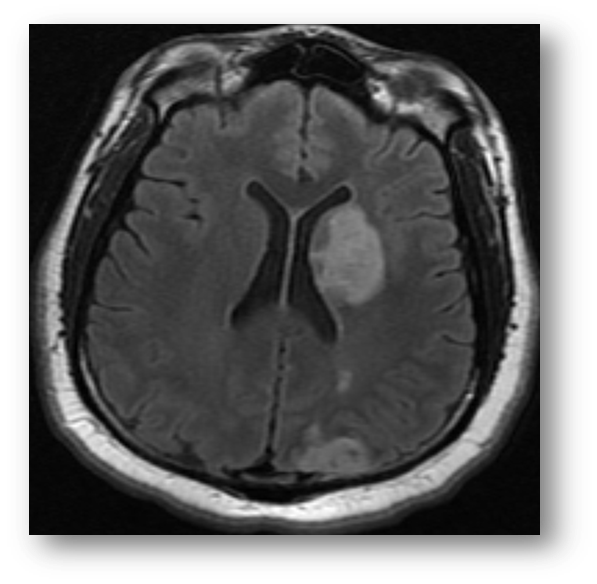

Refer to caption

Figure 1: T2 axial fast spin echo image showing acute ischemia in the PCA distribution. There is relative hyperintensity in the left occipital region of infarction. Note the prominent hyperintensity of the vitreous and cerebrospinal fluid, both consistent with the hyperintensity of water on T2-weighted imaging.

where Mxy(0)subscript𝑀𝑥𝑦0M_{xy}(0) is the transverse magnetization instantaneously after pulse excitation. Following the B1subscript𝐵1B_{1} induction of in-phase precession, the proton spins again begin to dephase according to T2subscript𝑇2T_{2} time constant. Of note, the relaxation of transverse magnetization is faster than the recovery of longitudinal magnetization. In other terms, T2<T1subscript𝑇2subscript𝑇1T_{2}<T_{1}. Figure (1) shows a T2 fast spin echo image of acute ischemic stroke in the posterior circulation.